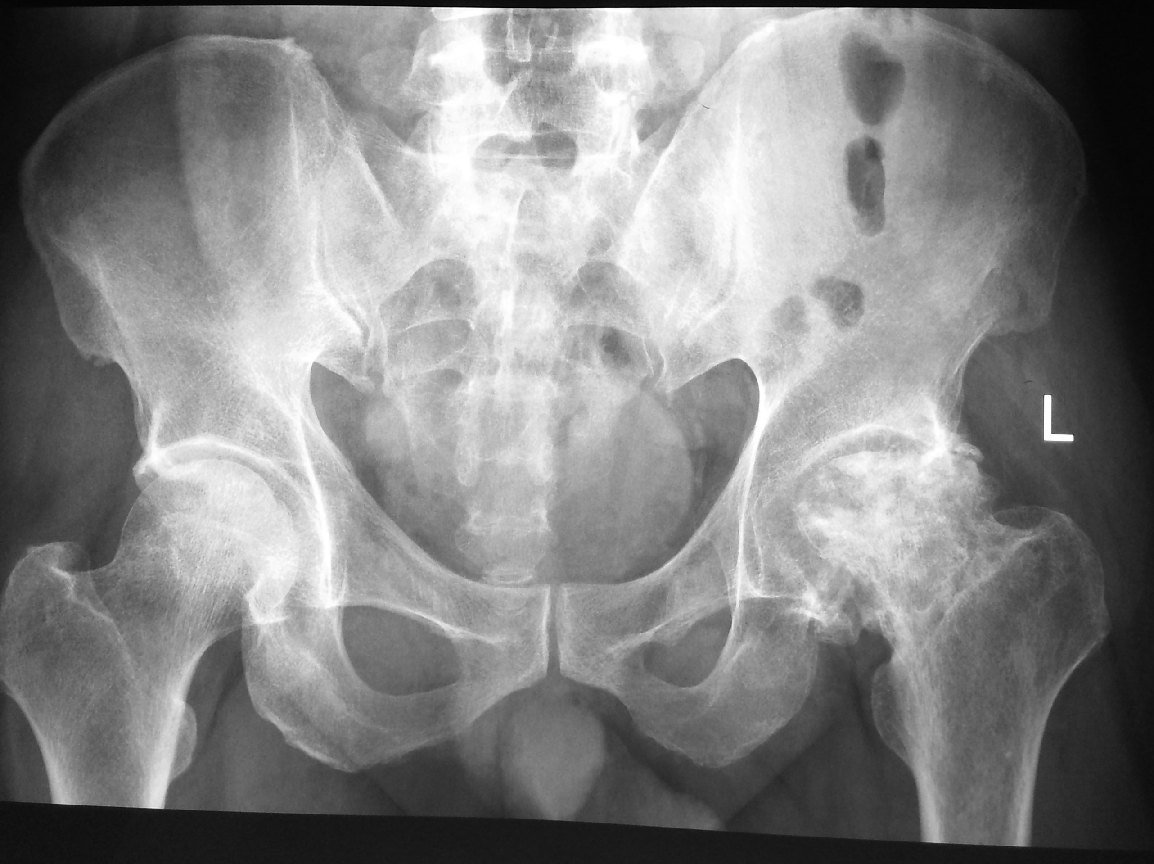

Investigations – X-rays of the pelvis and hip joint will usually clinch the diagnosis. In very early case of AVN hip, the x-rays of the hip may appear almost normal. In these cases, MRI scan of the hip may be required. MRI scan can also show us if there is any AVN disease in the contralateral hip. Bilateral hip AVN is not uncommon especially in those due to high dose steroid use.

This is a patient who was treated with high-dose steroid for almost 6 months for an auto-immune disease.

He presented with pain in his hip a year later. X-rays showed severe osteoarthritis of his left hip due to AVN.